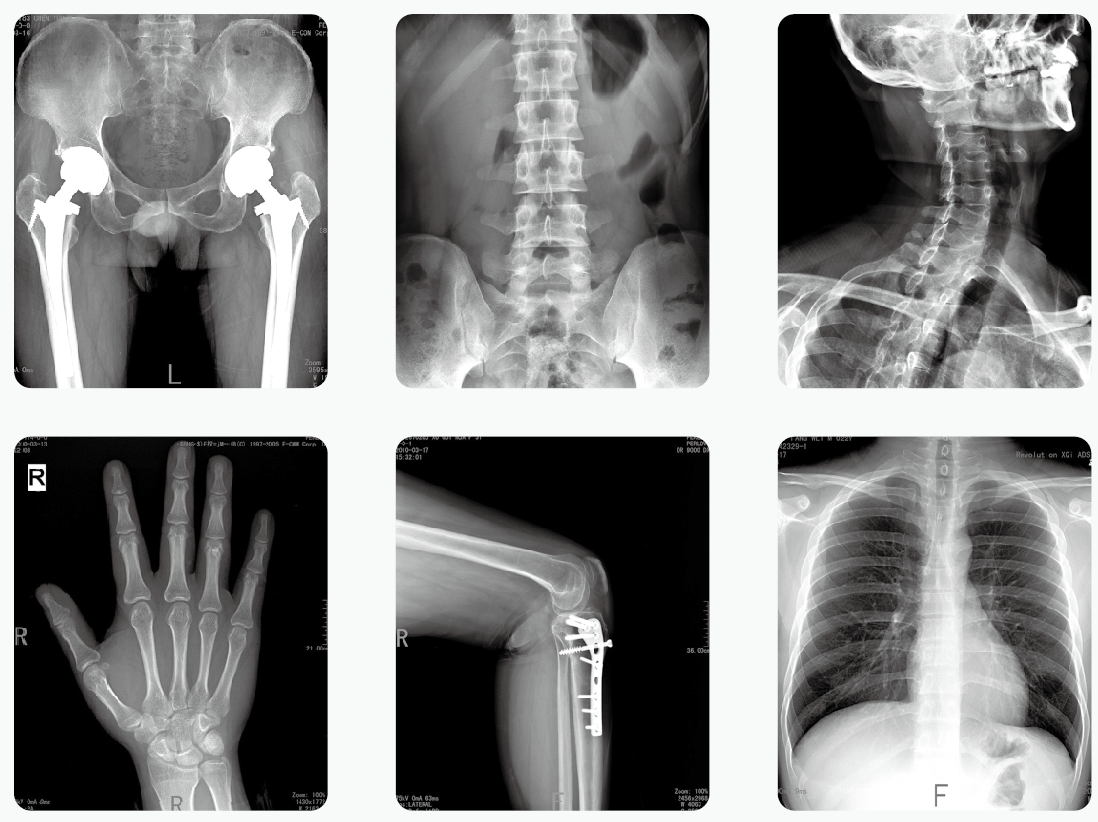

短期大劑量或長期小劑量接受放射檢查輻射,累積效應(yīng)可能導(dǎo)致細(xì)胞突變,與惡性腫瘤發(fā)病率正相關(guān),這已成共識。所以,不以劑量為前提談輻射危害都是在耍流氓!那么,多少劑量的輻射是安全的,是在可接受的范圍內(nèi)?

了解輻射的危害先要大概知道多大的輻射是相對安全的。人在地球上每時每刻都在接受輻射,輻射按照來源可以分為天然輻射和人工輻射。天然輻射就是來自大自然的輻射,包括太陽、空氣、地層等等散發(fā)的輻射。人工輻射則是人為制造的輻射,比如醫(yī)療器械檢查的輻射,核電站的輻射等。

放射檢查

世界衛(wèi)生組織的標(biāo)準(zhǔn)是:人體每年接受的輻射量不要超過5mSv(毫希伏)。

大家在單位例行體檢時一般會拍X光胸片,它的輻射量大約是0.1mSv;而做一次低劑量CT胸片是1mSv。

其實,大多數(shù)市民一年中也就是在體檢的時候才會接觸放射性檢查,不必過于擔(dān)憂。